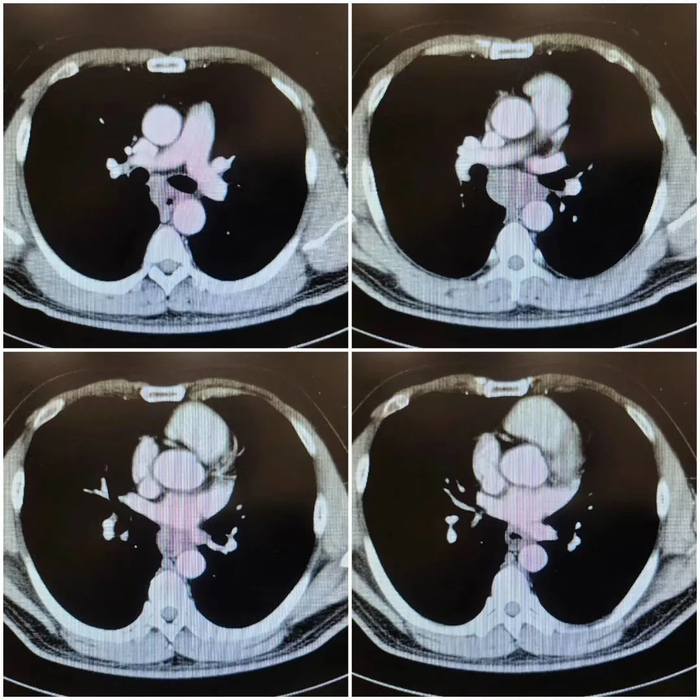

从ct图像上看,肿瘤位于食管右侧,从奇静脉弓水平至下叶静脉水平,从右

图片尺寸700x700